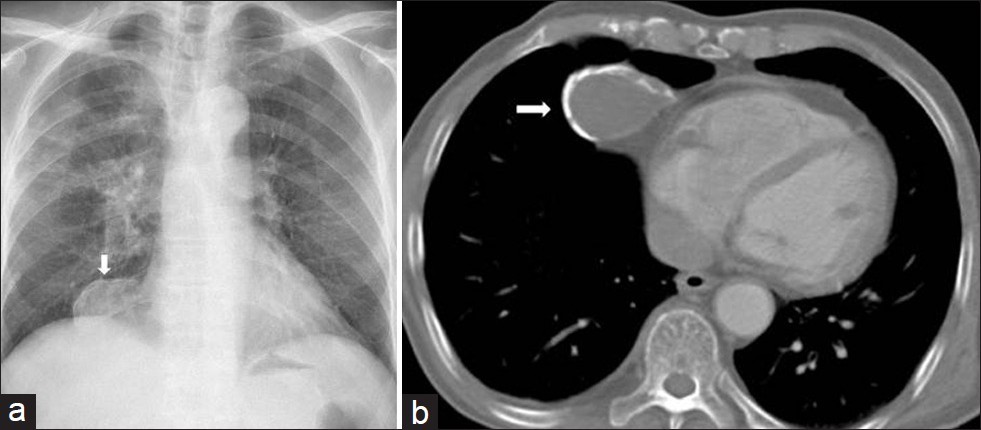

What is abnormal here?

This is a calcified pericardial cyst. A rimlike calcification is seen in the right cardiophrenic angle, an ideal location for pericardial cysts. These are usually asymptomatic and discovered when a CXR is obtained for another reason.